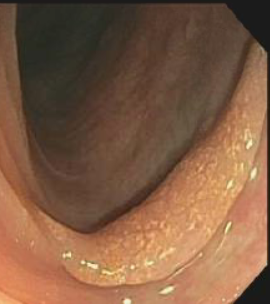

A colonoscopy showed a partially obstructing tumor in the proximal ascending colon, as well as multiple polyps (Figures 2 and 3).

Figure 3. Colonoscopy image showing a 20-mm polyp at the descending colon.